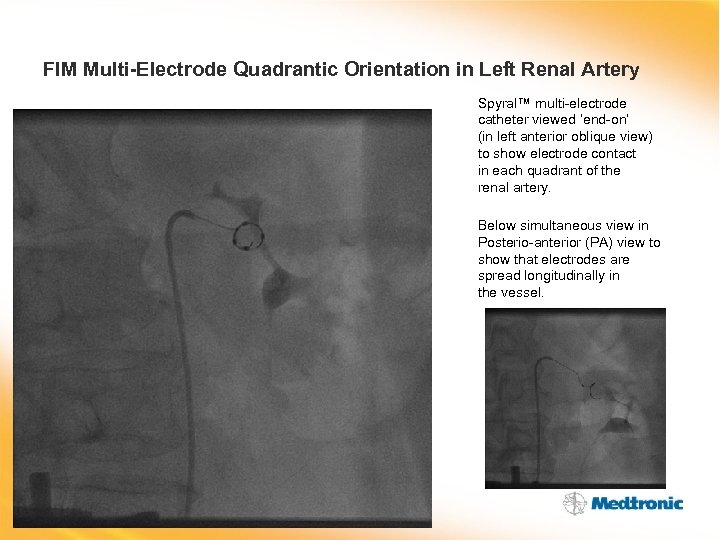

FIM Multi-Electrode Quadrantic Orientation in Left Renal Artery Spyral™ multi-electrode catheter viewed ‘end-on’ (in left anterior oblique view) to show electrode contact in each quadrant of the renal artery. Below simultaneous view in Posterio-anterior (PA) view to show that electrodes are spread longitudinally in the vessel.

FIM Multi-Electrode Quadrantic Orientation in Left Renal Artery Spyral™ multi-electrode catheter viewed ‘end-on’ (in left anterior oblique view) to show electrode contact in each quadrant of the renal artery. Below simultaneous view in Posterio-anterior (PA) view to show that electrodes are spread longitudinally in the vessel.